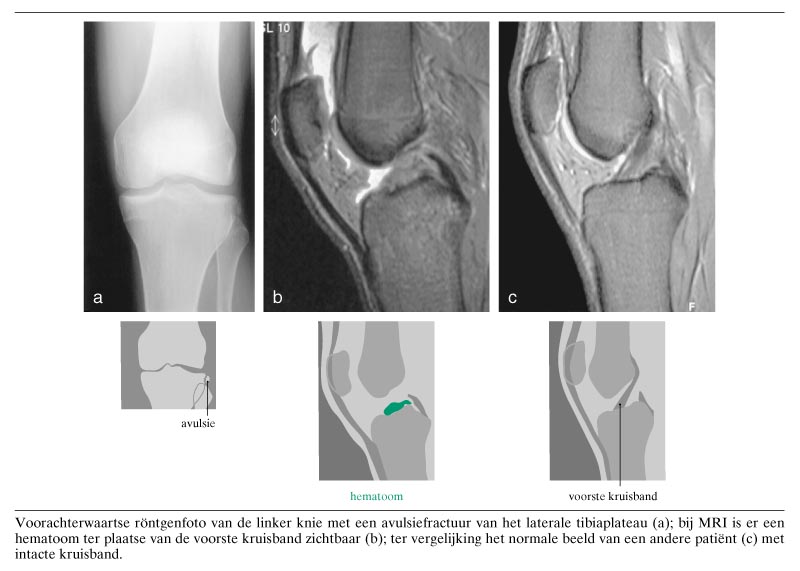

Een 23-jarige man was bij laad- en loswerkzaamheden hard op zijn gebogen linker knie gevallen. De knie werd langzaam dik, stijf en pijnlijk. Bij onderzoek werd hydrops van het gewricht geconstateerd. Het kniegewricht was aan de laterale zijde drukpijnlijk en in alle richtingen stabiel. Op een kniefoto was een avulsiefractuur van het laterale tibiaplateau zichtbaar (figuur). Deze fractuur berust op een avulsie van de laterale collaterale ligamenten en staat bekend als Segond-fractuur, genoemd naar Paul Segond, die in 1879 deze fractuur beschreef. Meestal ontstaat de fractuur bij endorotatie van het onderbeen bij een knie in flexie. Bij…